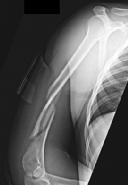

Figures 1 and 2 are the radiographs of a 19-year-old man with a closed right humeral shaft fracture as well as a right femoral shaft fracture and a left ankle fracture-dislocation after a motor vehicle collision. On initial examination, he is noted to have a complete radial nerve palsy of his right upper extremity.

Postoperative radiographs are shown in Figures 3 and

The working length of the plate is best described as the length